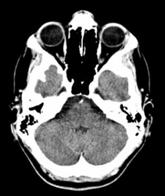

Figure 1. Simplified Tomography flow. Scanning (left) produces a set of aggregate data on probe lines. Through back-projection (center) multiple samples are brought together to reconstruct the internal structure of the patient (right).

In

tomographic systems, the primary computational demand after data capture by the

scanner is the backprojection of the acquired data into image space to

reconstruct the internal structure of the scanned object (Figure 1 middle).